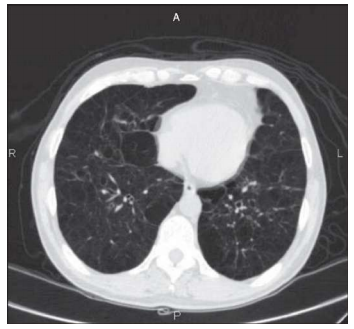

Um homem de 66 anos de idade, tabagista (carga tabágica de 150 maços/ano), portador de insuficiência cardíaca, diabetes e hipotireoidismo, procurou ajuda, no hospital local, por tosse, com expectoração amarelada, e piora da dispneia basal há dois dias. Nega febre. Ao exame, encontrava-se emagrecido e hidratado, com ACV: RCR em dois tempos, bulhas normofonéticas, FC de 80 bpm, MV+ bilateralmente, com sibilos esparsos e roncos, FR de 30 irpm e membros inferiores sem edemas. Laboratório: Hb 15.8; leucócitos 9.000, sem desvios; PCR 5 (ref. 0,5); Cr 1.5; UR 60; glicose 146; Na+ 146; e K+ 4.6. Gasometria: pH 7.3; PaCO2 60; HCO3 30.2; BE+ 7; e sat. de O2 de 87% em ar ambiente. Realizou a tomografia de tórax mostrada a seguir.

Com base nessa situação hipotética, assinale a alternativa que apresenta, correta e respectivamente, o diagnóstico mais provável e a conduta a ser adotada.